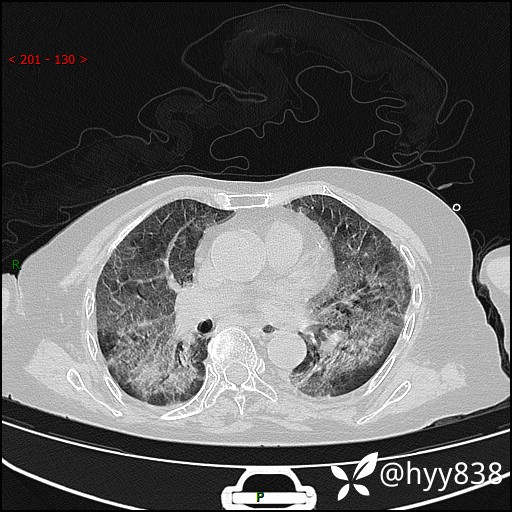

弥漫性肺部病变,辗转当地多家医院未能确诊,拟诊“重症肺炎”入我院--结果公布

患者年龄:69岁

简要病史: 患者20余天前无明显诱因出现发热,最高体温37.5℃,伴头晕,乏力,纳差等不适,无鼻塞,流涕,无咳嗽咳痰,无呼吸困难,无恶心呕吐、关节疼痛等不适,于当地市多家医院就诊,未明确病因,2023.6.23于当地第二人民医院就诊,完善胸部CT示病毒性肺炎,予以抗感染、清热解毒后症状较前稍好转,2天前患者无明显诱因出现活动后喘息加重,伴肌肉酸痛,口干,无明显咳嗽咳痰,今日体温38.1℃,为求进一步诊治来我院就诊,门诊以“ 重症肺炎 I型呼吸衰竭”收入院。 患者起病以来,精神、睡眠、饮食欠佳,大小便正常,体力下降,体重无明显改变。

辅助检查:CT

临床诊断:重症肺炎

胸部CT薄层扫描